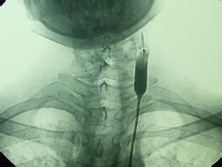

頸靜脈球瘤(非嗜鉻性副交感神經(jīng)節(jié)瘤、化學(xué)感受器瘤、類頸動(dòng)脈體瘤)

頸靜脈球瘤是發(fā)生在顱底頸靜脈孔內(nèi)及其附近的腫瘤,病程從1個(gè)月到28年不等,以后組腦神經(jīng)受累為主,多為單發(fā)性腫瘤,很少有家族性遺傳傾向。目前該病理想的治療方法是手術(shù)切除腫瘤。Guilol和Rosenwasser(1940)首先報(bào)告頸靜脈球瘤手術(shù)切除,但由于腫瘤組織供血豐富,局部解剖復(fù)雜,給手術(shù)切除腫瘤增加了難度。

• 應(yīng)該做哪些檢查項(xiàng)目呢?腦血管造影、頭部CT